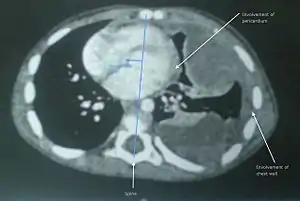

Diagnosis

The only reliable way to determine whether a soft-tissue tumour is benign or malignant is through a biopsy. The two methods for acquisition of tumour tissue for cytopathological analysis are:

A pathologist examines the tissue under a microscope. If cancer is present, the pathologist can usually determine the type of cancer and its grade. Here, 'grade' refers to a scale used to represent concisely the predicted growth rate of the tumour and its tendency to spread, and this is determined by the degree to which the cancer cells appear abnormal when examined under a microscope. Low-grade sarcomas, although cancerous, are defined as those that are less likely to metastasise. High-grade sarcomas are defined as those more likely to spread to other parts of the body. For soft-tissue sarcoma, the two histological grading systems are the National Cancer Institute system and the French Federation of Cancer Centers Sarcoma Group system.[6][7][8]

Soft-tissue sarcomas commonly originate in the upper body, in the shoulder or upper chest. Some symptoms are uneven posture, pain in the trapezius muscle, and cervical inflexibility [difficulty in turning the head].

The most common site to which soft-tissue sarcoma spreads is the lungs.